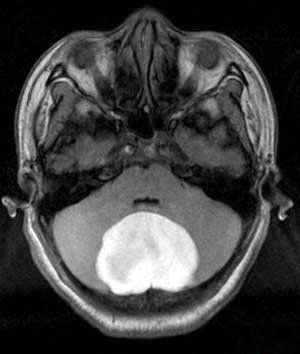

颅内畸胎瘤MRI